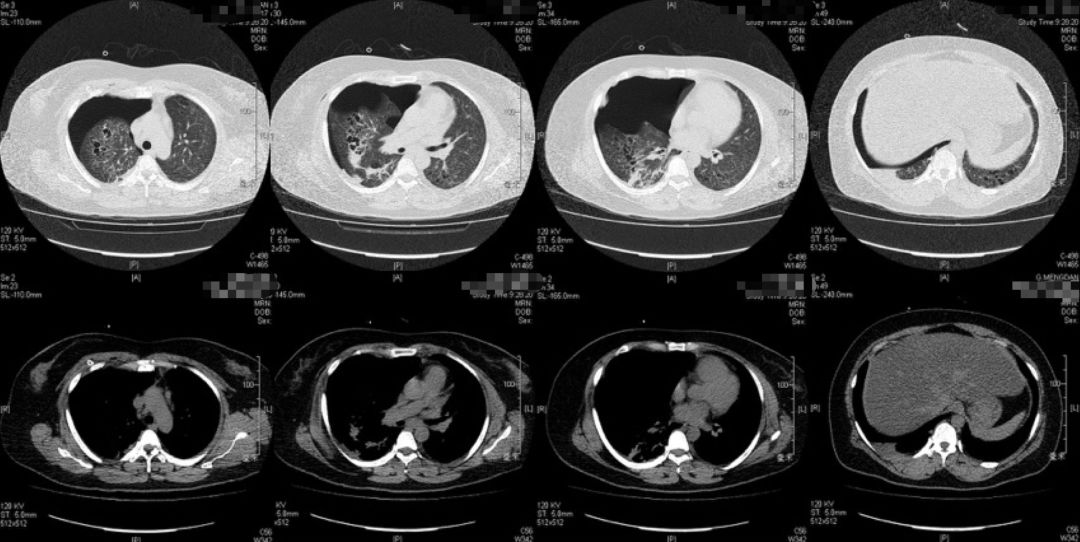

5-16胸片

5-17胸部LDCT

本例患者的胸部CT主要表现为两肺相对弥漫分布的怪异的气囊和结节,气囊为薄壁,以中上肺分布为主,沿支气管血管束分布,符合LCH细胞沿支气管分布的特点,并且有可能会引起支气管阻塞,类似活瓣样的作用,因此囊腔的形状怪异。胸腔镜术后的CT表现,可能是局部阻塞牵拉引起疱的加重,也可能是胸膜粘连后局限性的气胸的表现。